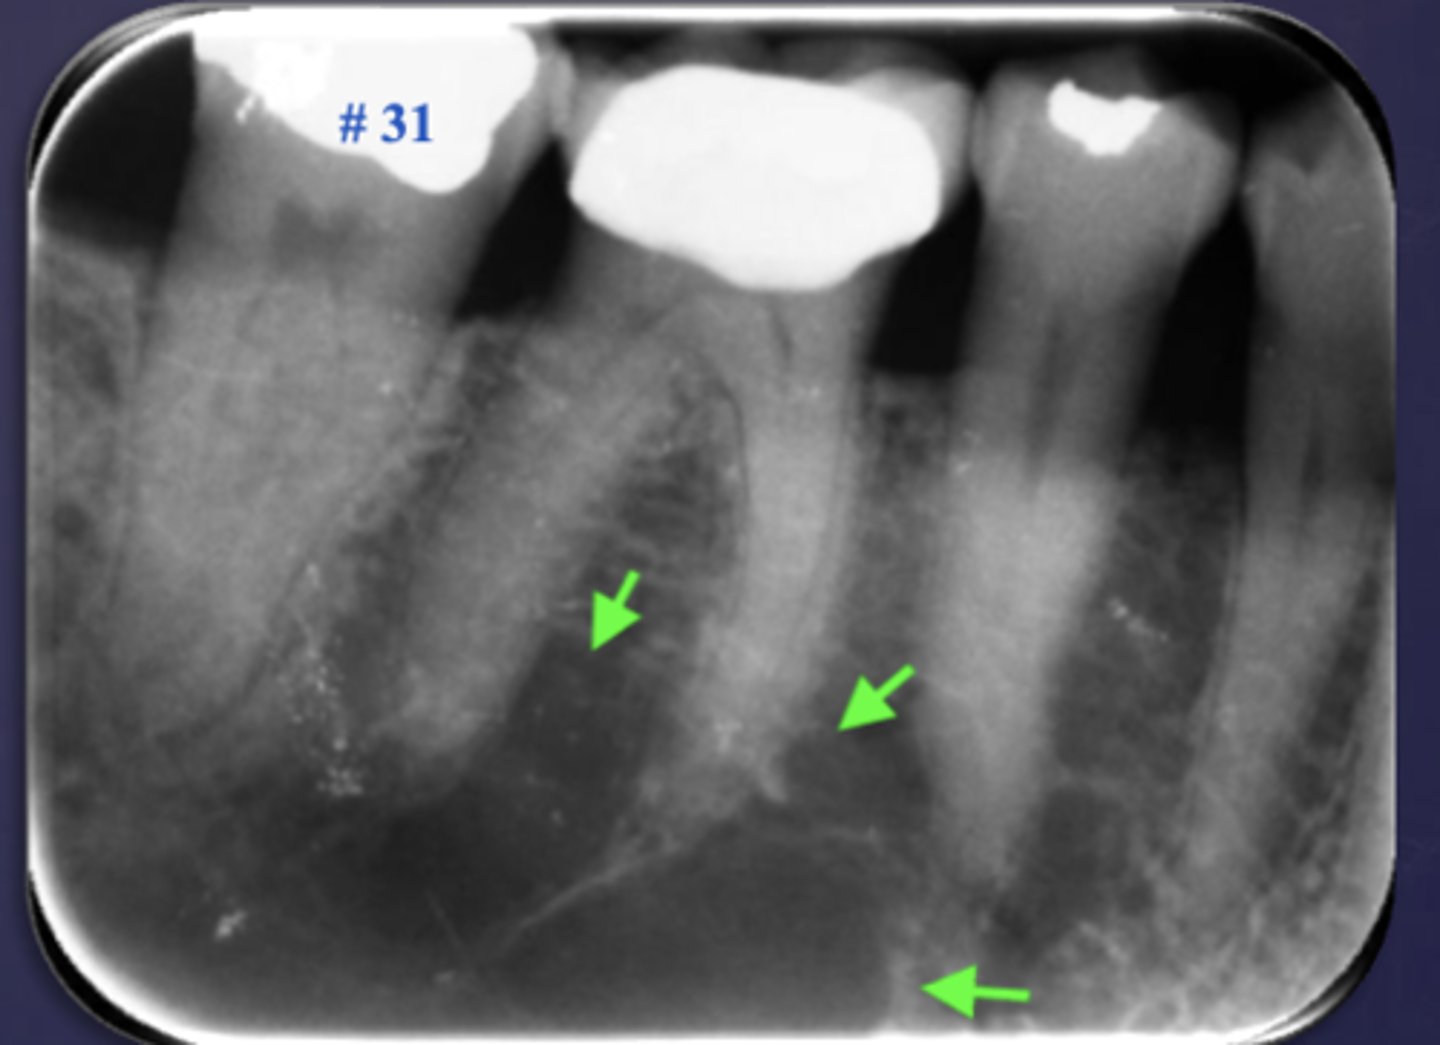

What are two defects that the arrows are pointing to?

- Widened PDL

- Sclerosis